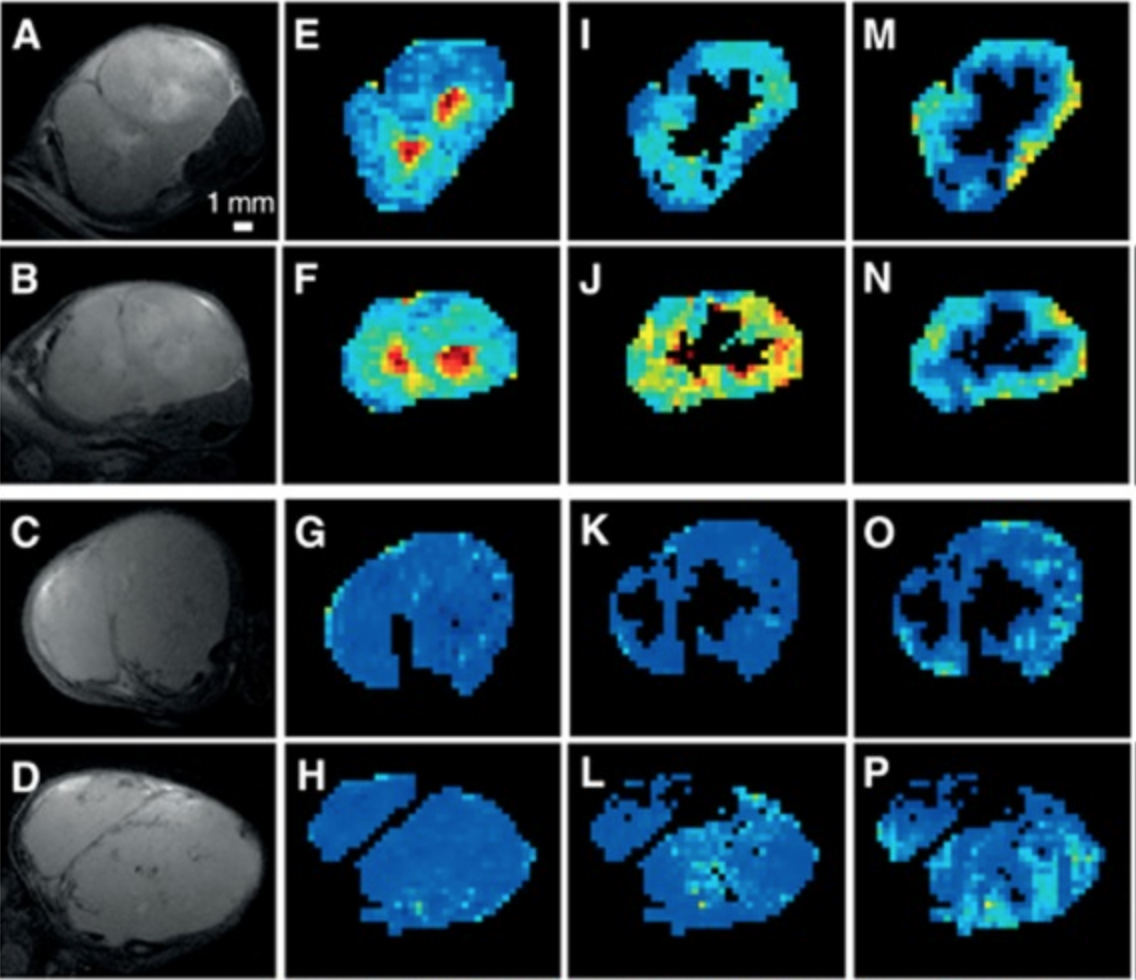

The phosphoinositide-3 kinase (PI3K) pathway is an attractive therapeutic target. However, difficulty in predicting therapeutic response limits the clinical implementation of PI3K inhibitors. This study evaluates the utility of clinically relevant magnetic resonance imaging (MRI) biomarkers for noninvasively assessing the in vivo response to the dual PI3K/mTOR inhibitor BEZ235 in two ovarian cancer models with differential PI3K pathway activity.